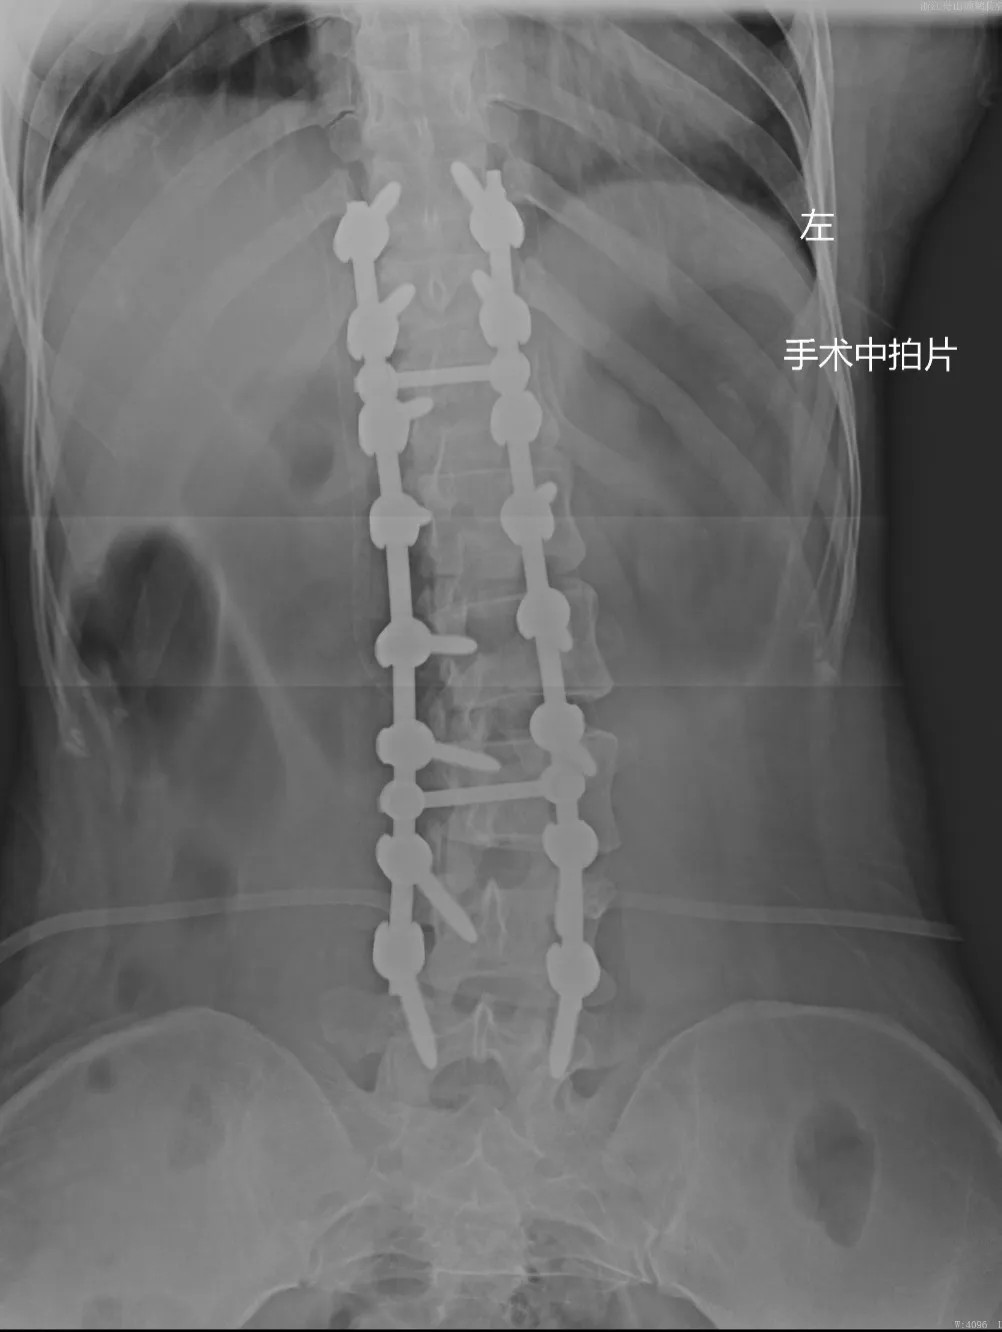

在充分的術(shù)前準(zhǔn)備后,脊柱科、微創(chuàng)治療中心專家團(tuán)隊為文女士(化名)進(jìn)行了脊柱側(cè)彎矯形、植骨融合內(nèi)固定術(shù),歷經(jīng)近4個半小時的精細(xì)操作,手術(shù)圓滿完成。術(shù)中全程使用術(shù)中電生理監(jiān)測系統(tǒng),每步都力求精準(zhǔn)細(xì)致。

近日,文女士(化名)來院復(fù)診,整體恢復(fù)良好,術(shù)前活動不便的癥狀明顯好多了,腰背部肌肉也恢復(fù)了一些,脊柱生理曲度相比術(shù)前有所恢復(fù),側(cè)彎癥狀也明顯改善,下胸椎、腰椎向左側(cè)側(cè)凸畸形較前改善,腰背部轉(zhuǎn)側(cè)活動不利較前改善。